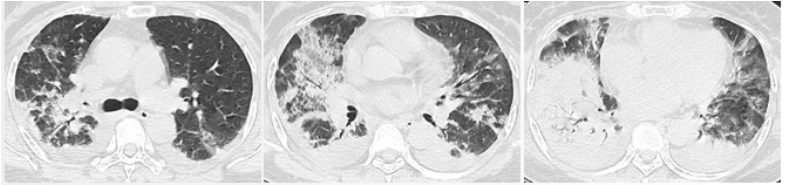

患者,女,50岁;活动后喘息20天,加重伴发热3天,2021年11月19日转入我院。入院胸部CT显示:双肺实变,磨玻璃影(图1)。11月24日复查胸部CT可见病变进展迅速(图2)。予患者气管插管机械通气、俯卧位等,呼吸衰竭未见改善。遂于11月25日启动VV-ECMO(转速2860 rpm,流量4.5 L/min,氧浓度100%)。追问病史:患者入院前1月有活动后气促症状,自觉全身不适,近2年有眼干、口干不适。进一步检查发现,ANA反应阳性(+),ANA核型为胞浆颗粒型(异常);抗SSA/Ro抗体阳性(++)、抗Ro-52抗体阳性(+++)。诊断:急性间质性肺炎(AIP);Ⅰ型呼吸衰竭;混合性结缔组织病。治疗:VV-ECMO+呼吸机辅助通气+俯卧位通气、激素(甲强龙80 mg×7天,60 mg×3天,40 mg qd)、免疫抑制剂(环磷酰胺400 mg qd×3天)、抗感染(哌拉西林他唑巴坦4.5 g q12h+莫西沙星0.4 g qd+氟康唑氯化钠注射液20 mg qd)、抗凝等。在随后的一段时间内,患者影像学改善不明显(图3)。直至12月20日,复查胸部CT可见患者肺部病变较前明显吸收(图4)。2021年12月31日VV-ECMO撤机后,继续气切呼吸机辅助通气,甲强龙40 mg qd抗炎治疗,继续抗感染治疗,2022年1月7日脱机,1月21日气管封管,1月26日出院。后续治疗:强的松25 mg qd,环磷酰胺600 mg q2w×4次,序贯吗替麦考酚酯0.5 g bid。重症间质性肺疾病(ILD)在诊断方面需要考虑以下问题:是ILD吗?是哪种ILD?严重程度如何?在治疗方面,除了生命支持(呼吸支持重点)和病因治疗,并发症的处理也至关重要。重症ILD的诊断包括两方面,一方面是通过影像学、病史+临床表现、BALF-NGS、实验室检查、肺活检等对ILD进行诊断;另一方面涉及重症,患者多面临呼吸衰竭甚至多器官衰竭,因此时间更加紧迫。在ICU内最常见的重症ILD包括:特发性肺纤维化急性加重(AE-IPF)、自身免疫相关性ILD、肿瘤治疗相关性ILD、隐源性机化性肺炎(COP)、AIP、过敏性肺炎(HP)、急性嗜酸性粒细胞性肺炎(AEP)、药物相关ILD等。在影像学方面,最易导致重症的类型有弥漫性磨玻璃影和实变影。最常见的鉴别诊断就是重症肺部感染。表现为弥漫性磨玻璃影或实变影的ILD较为多见,例如:HP、嗜酸性粒细胞性肺炎(EP)、结缔组织病相关间质性肺病(CTD-ILD)、非特异性间质性肺炎(NSIP)、脱屑性间质性肺炎(DIP)、淋巴细胞性间质性肺炎(LIP)、机化性肺炎(OP)、AE-IPF、肺泡蛋白沉积症(PAP)、肺泡微结石症、结节病、弥漫性肺泡出血综合征、肺水肿等。而很多感染性疾病影像学也可表现为磨玻璃影,例如:卡氏肺孢子菌肺炎(PCP)、病毒性肺炎、巨细胞病毒性肺炎、支原体肺炎。尽管如此,ILD也有部分影像学具有特征性,可以被识别。图5左表现为肺陷闭,也称为“猪头肉冻征”,这是典型的亚急性HP的影像学特征。图5右表现为弥漫性磨玻璃影,但以肺门向外扩展,外面有肺大泡,这是典型的PCP表现。临床上多见自身免疫性疾病导致的ILD,此类疾病也具有共同的特征,例如双肺弥漫,病理方面以NSIP或OP为主要特征。但也有部分患者可以出现弥漫性肺泡损伤(DAD)特征。如图6所示,左图为ANCA相关性血管炎,右图为MDA5相关性间质性肺病。因此,一定要警惕容易发生这种病理改变的自身免疫性疾病。